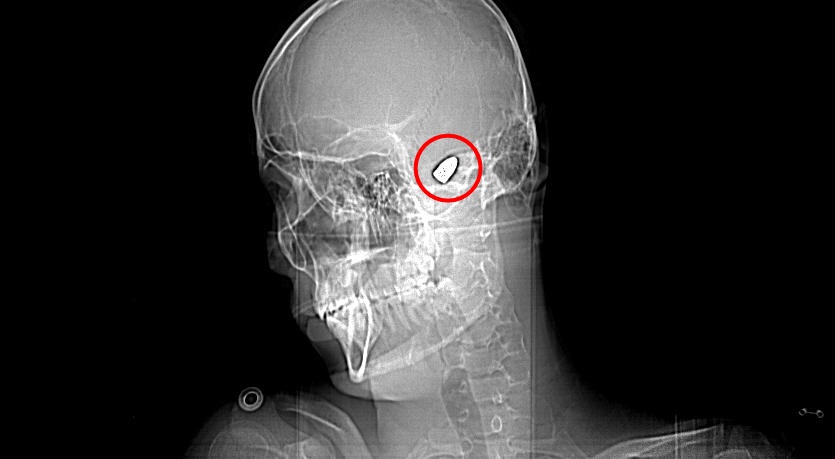

Çevredekilerin hastaneye götürdüğü Yusuf’un çekilen röntgeninde, başında mermi çekirdeği olduğu tespit edildi.

Doktorlar Yusuf'un başındaki merminin riskli bir bölgede olması sebebiyle çıkarılamayacağını söyledi. 4 gün yoğun bakım, 4 gün de serviste tedavi gören Yusuf düzenli olarak doktor kontrollerine gitti.